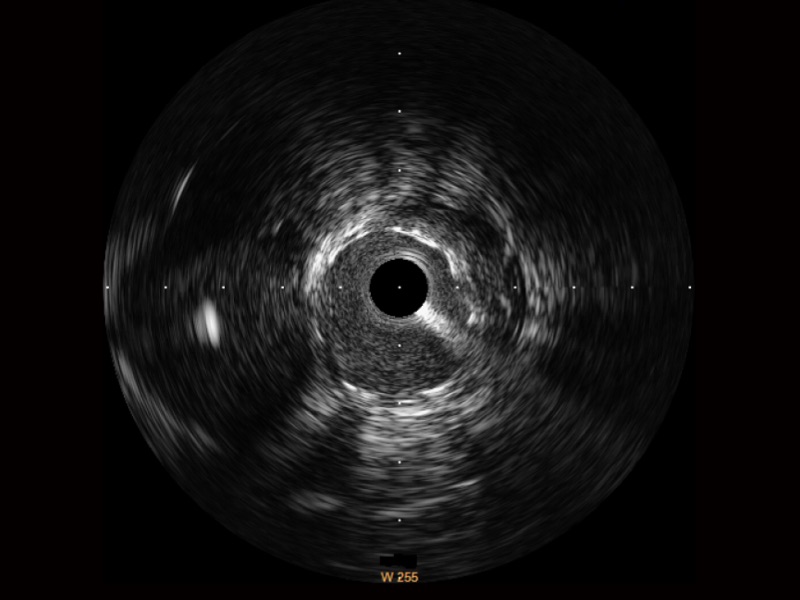

• 百老汇电子游戏官网宽频IVUS图像

• 传统IVUS图像

对比传统IVUS导管成像,百老汇电子游戏官网宽频IVUS图像的近场支架梁显影更细腻,远场中膜外血管仍清晰可辨,兼顾远中近,兼顾分辨力与穿透深度